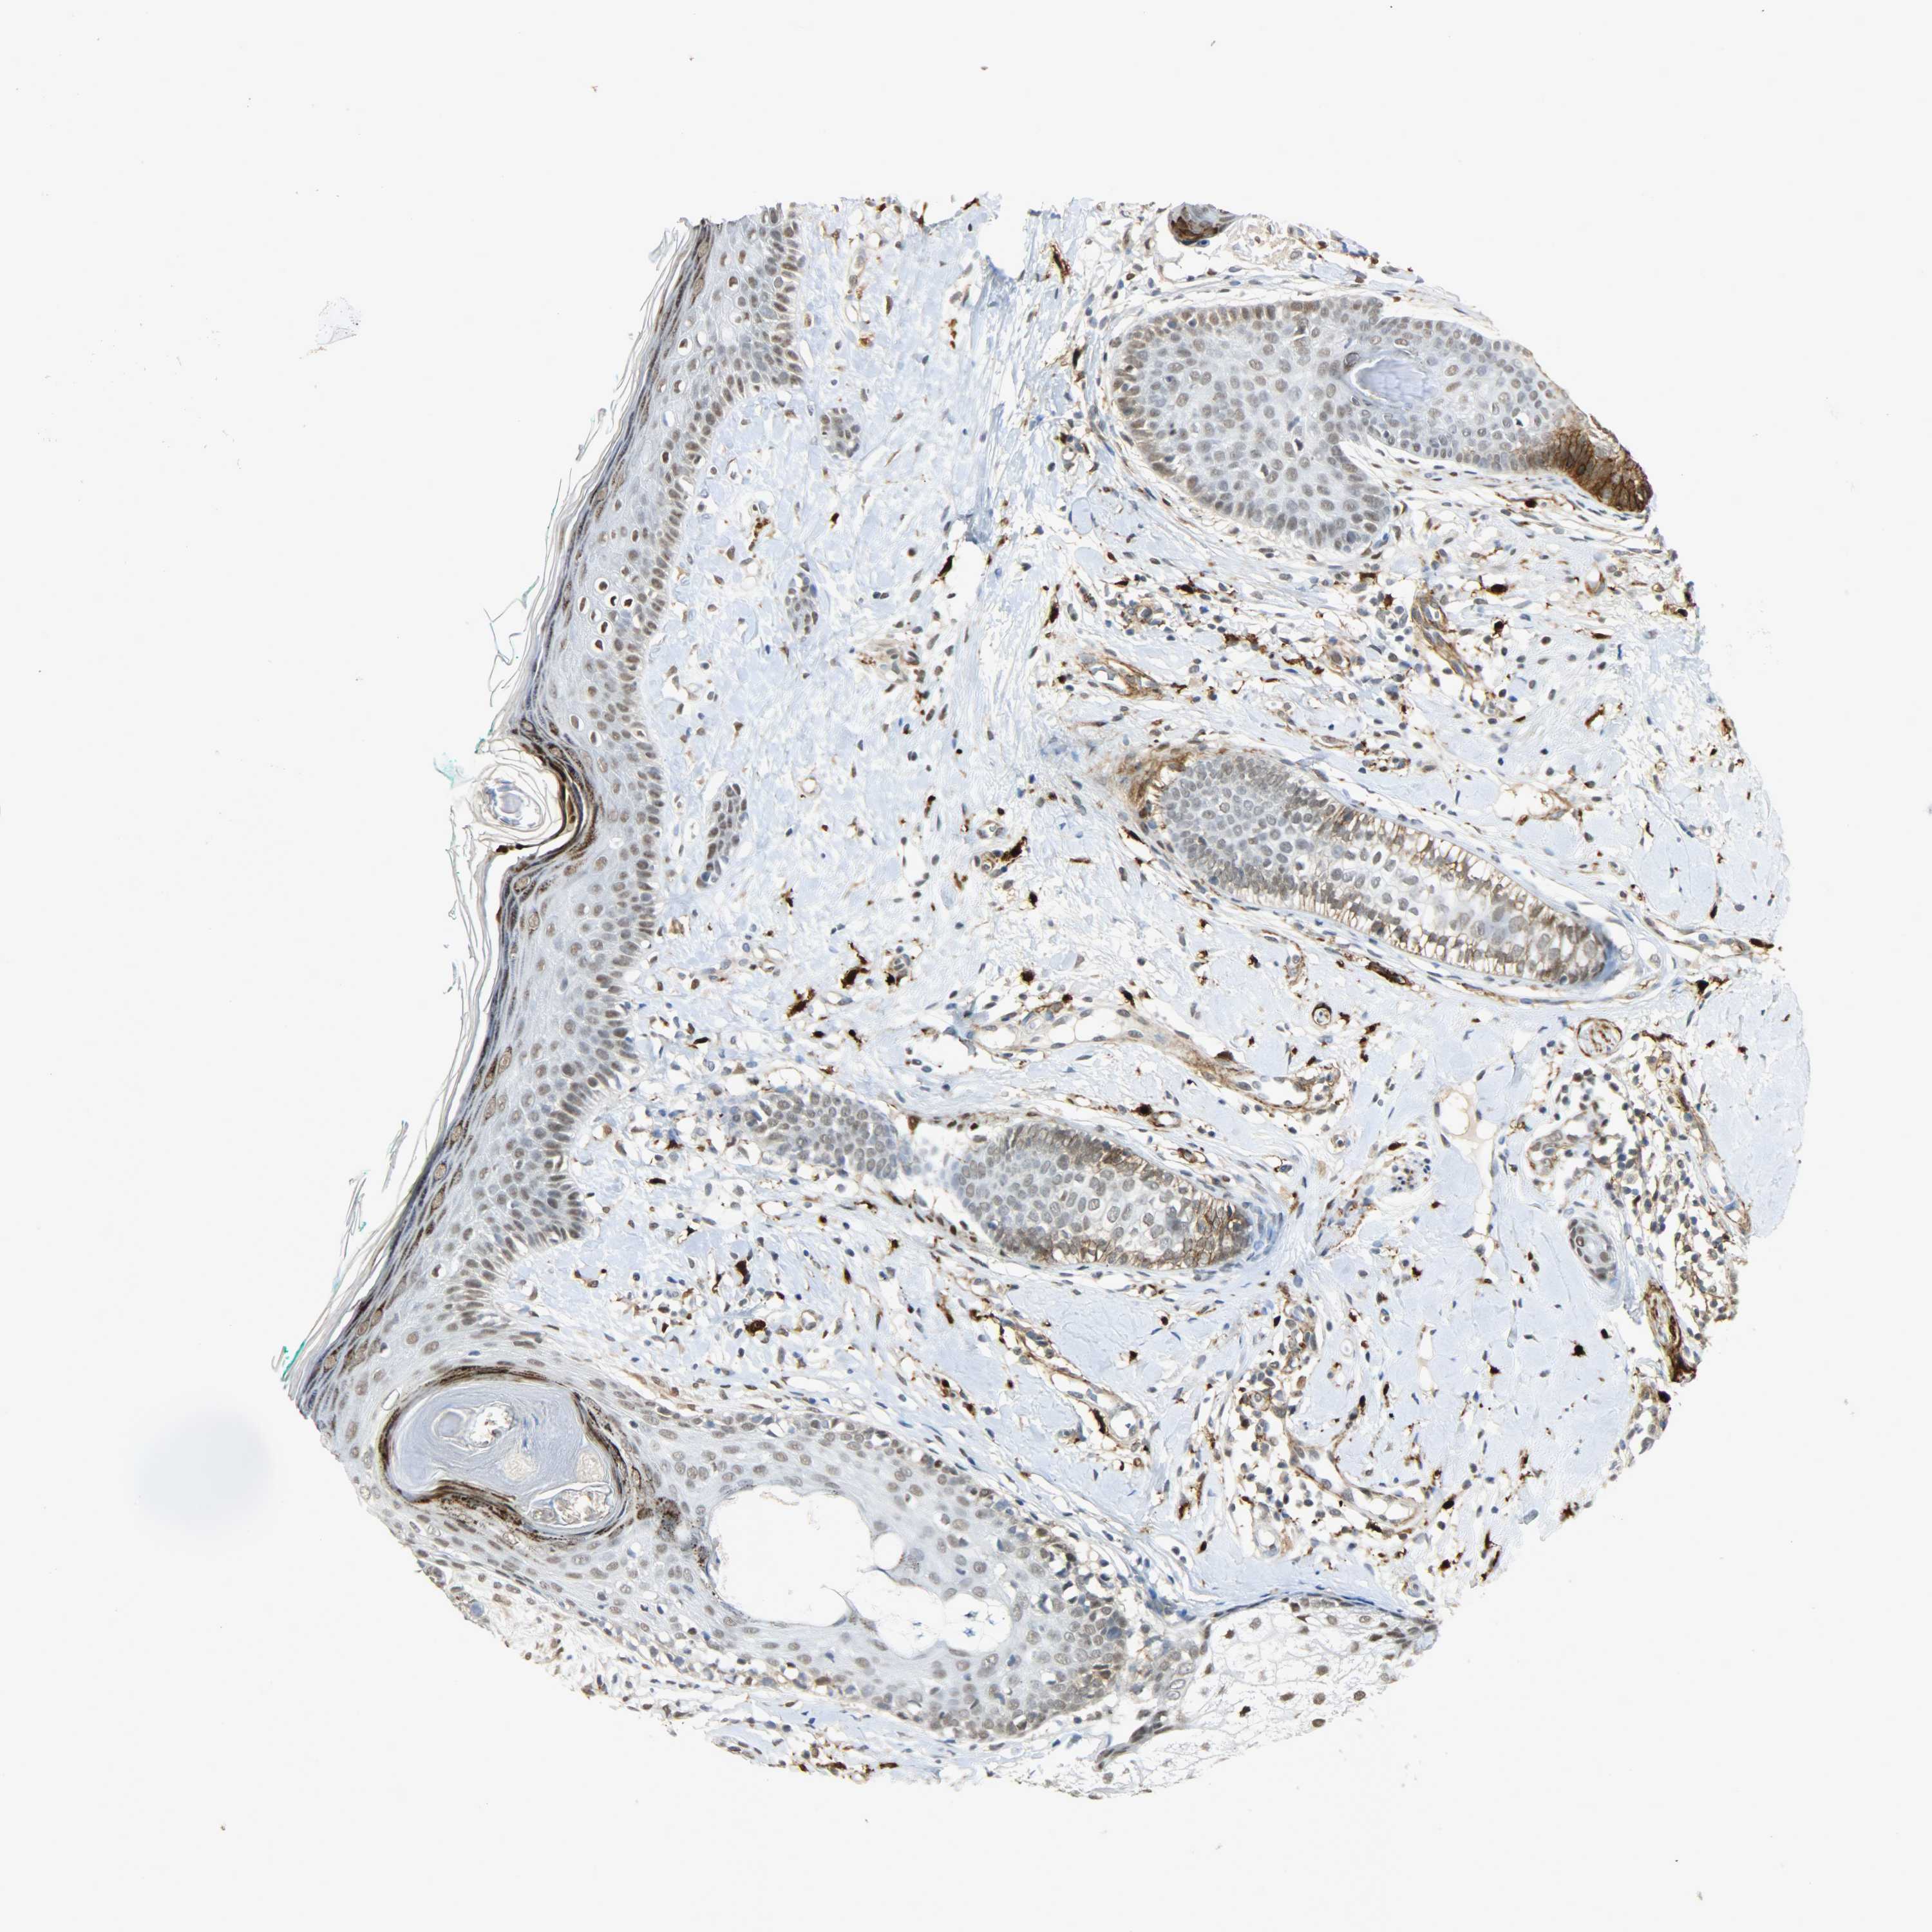

SKIN CANCER - Protein expressioni

A mouse-over function shows sample information and annotation data. Click on an image to view it in a full screen mode. Samples can be filtered based on level of antibody staining by selecting one or several of the following categories: high, medium, low and not detected. The assay and annotation is described here.

Each image is clickable and will lead to virtual microscopy that enables deeper exploration of all samples and also displays staining intensity scores, fraction scores and subcellular localization as well as patient and tissue information for each sample.

Antibody HPA004765

Staining

High

Medium

Low

Not detected

Intensity

Strong

Moderate

Weak

Negative

Quantity

>75%

75%-25%

<25%

None

Location

Nuclear

Cytoplasmic/membranous

Cytoplasmic/membranous,nuclear

Squamous cell carcinoma, NOS

Basal cell carcinoma